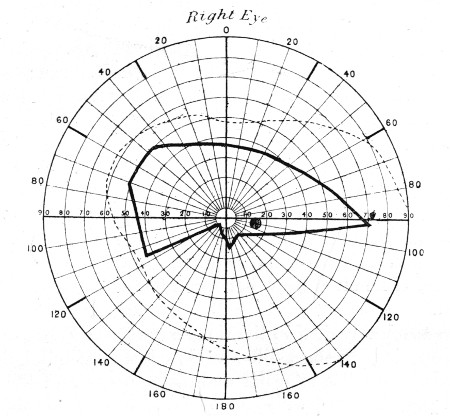

76. " " " 281

77. " " " 283